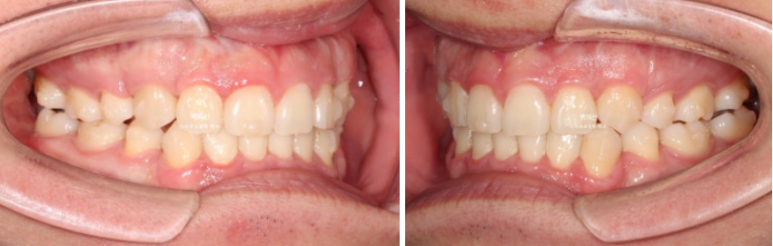

24년 10월, 돌출입 수술 한달 후 내원한 환자분 입니다.

24.10

돌출입 수술을 하면 수술 테크닉적으로 작은어금니가 있던 공간이 약 2mm 이상이 남게 됩니다.

송곳니 뒤쪽에 2mm 의 공간이 각각 남았습니다.

전 후 비교 보겠습니다.

24.10~25.08

이제 전 후 비교 보겠습니다.

앞니가 깊게 물리는 과개교합도 좋아졌습니다.